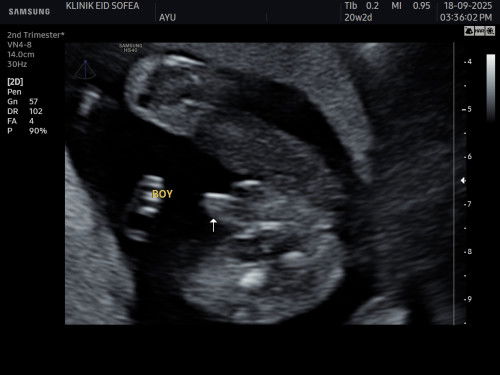

its a boy?

scan 20w, menunjukkan pistol… ad x mommies scan pistol, tp kluar girl.. kita nak kemas2 baju2 girl kakak nya pnya, nk bagi sedara mara.. tp masih dilema lagi, tkot kne scam..